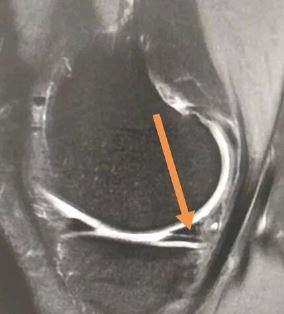

2级(II级):半月板内部出现线形的中等信号增高影,可延伸到半月板的关节囊缘,未达半月板表面。

(II级:半月板内部线行高信号,未达半月板的上或下表面)